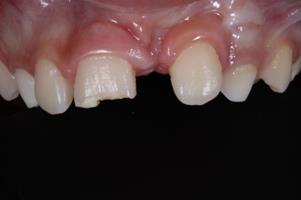

Paciente do sexo masculino, 8 anos de idade, compareceu ao Pronto Atendimento Odontológico Infantil da Clínica de Especialidades Infantis-Bebê-Clínica da Universidade Estadual de Londrina, para tratamento imediato após fratura no incisivo central superior direito devido a queda durante atividade esportiva escolar. Ao exame físico intrabucal, foi diagnosticada fratura coronária do esmalte e da dentina sem comprometimento do tecido pulpar (Figura 1). A resposta ao teste de percussão vertical e horizontal não foi sugestiva de alterações endodôntica e periodontal, respectivamente, e o comprometimento da inserção periodontal também foi descartado por meio do teste de mobilidade no sentido vestíbulo palatino. O exame radiográfico (Figura 2) ratificou o não comprometimento periodontal e periapical, bem como, a não fratura radicular.